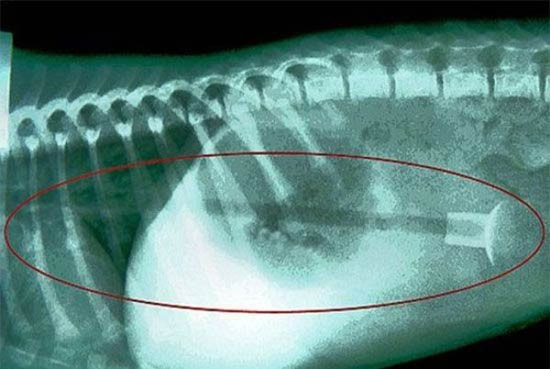

Köpeğin midesinden çıkana bak!